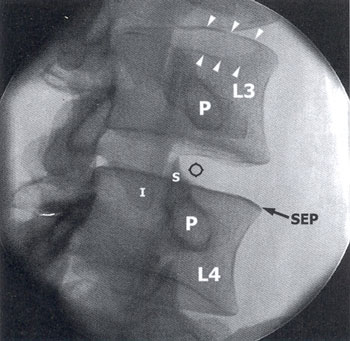

Outro método possível de obter o ponto de entrada do fio guia é utilizando uma imagem oblique em 45o, sendo que o ponto de entrada deve localizar-se logo lateral à faceta (Fig. 4), de modo a penetrar exatamete na zona triangular de segurança.

Fig. 4